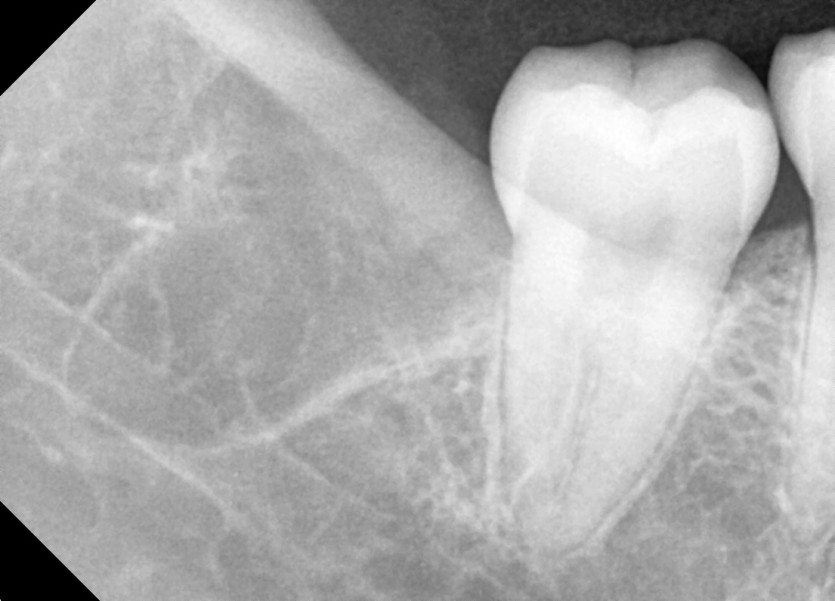

#48 사랑니 발치

구강 외과 전문의가 당일 발치했습니다.